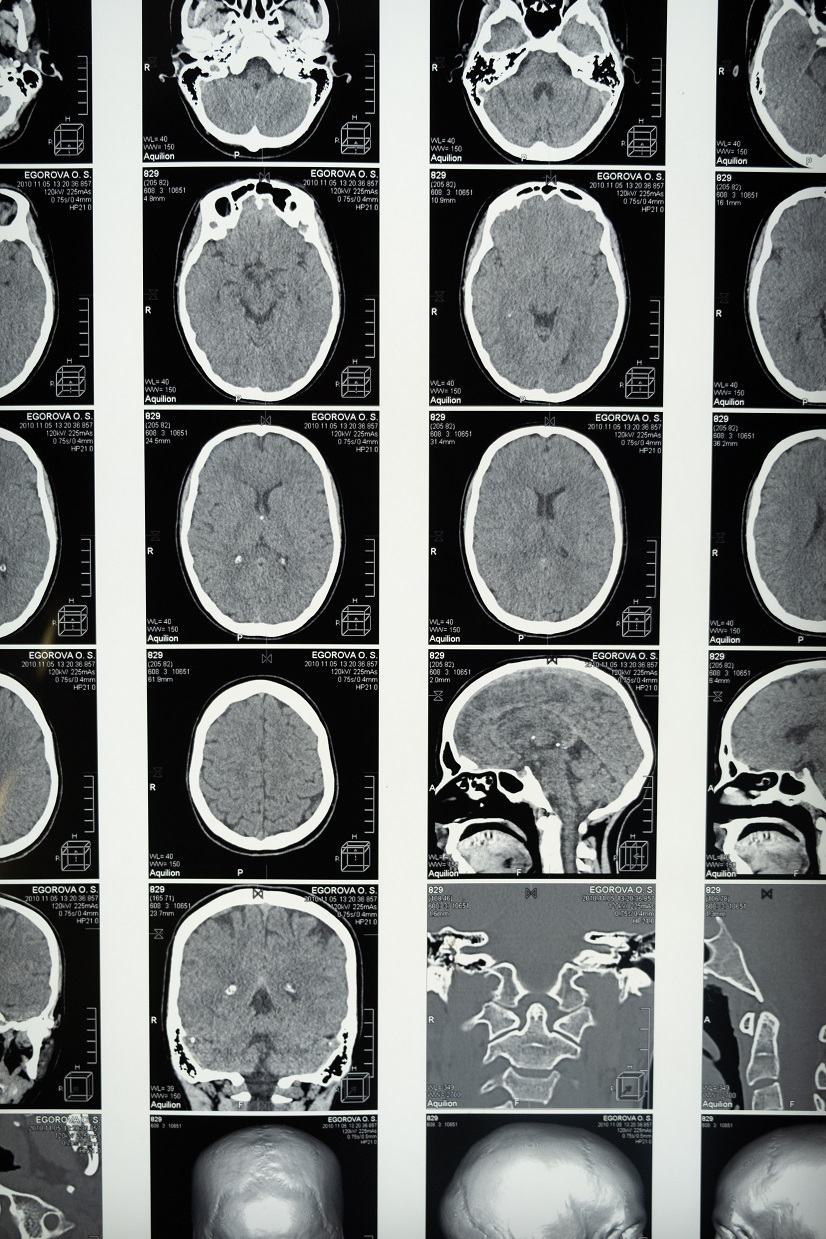

COVID Can Lead to Brain Damage and Cognitive Impairment

Studies have shown the coronavirus can have a permanent impact on the brain.

The coronavirus impacts the brain – big time.  And research shows this is what’s happening even during mild COVID cases when patients lose their sense of smell.  In early studies, the loss of smell alone seemed to be, in and of itself, an adequate-enough sign that an individual has contracted the novel virus.  Furthermore, it was a sufficient predictor that the upper respiratory distress a patient was presenting with was caused by COVID.  Contrary to an early belief that the loss of smell would be temporary and pass when a patient no longer tested positive, many people have reported prolonged lacking this sense even long after the infection has run its course.  Thus, researchers became determined to find the reasoning behind lingering symptoms, and it is now known that the nervous system is impacted.  Brain damage can occur.

Late last month, an article published in JAMA Network Open, sought to use data from spinal taps to determine exactly how the brain is affected.  The virus is commonly known to cause brain fog, extreme fatigue and problems with concentration and memory.  These issues are linked to what has been coined “long COVID.”  COVID can cause brain damage and subsequent neuropathy and delirium.

Scientists collected data from the UK Biobank database, “looking at brain magnetic resonance imaging (MRI) scans and tests of brain function in 785 volunteers.”  They discovered, “About half of those participants had mild COVID infection, and the other half had contracted the virus.   This allowed the team to determine the effects of mild COVID infection on brain structure and function.”  In doing so, the team found that those with only a mild infection experienced some brain shrinkage.